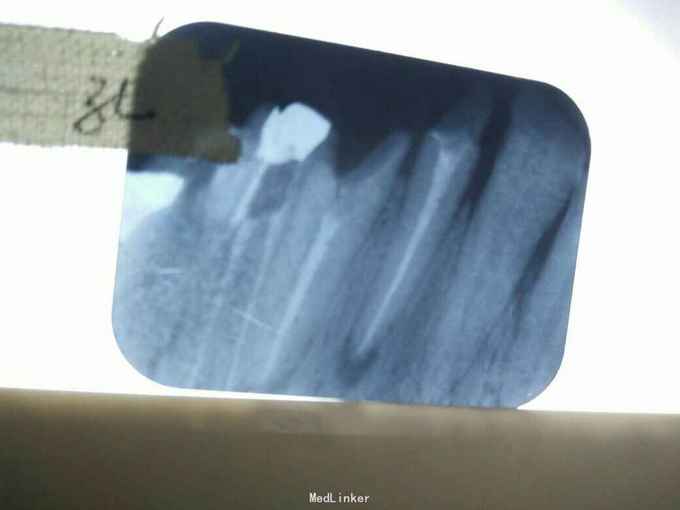

检查: 12-16可见冠修复体;12-15烤瓷冠;16金属冠;12,13连冠;14,15,16连冠;12,14,15頰侧根尖部有3个粟粒大小的乳头状牙龈窦道,挤之有脓液溢出,牙无明显松动,冷热诊无反应,叩(++),其余无异常 x线片示:12-15根尖部有形状不规则,边缘模糊的透射阴影区,14,16牙根内有高密度阻射物,14可腭根欠填 全口口腔卫生良,牙石I度,色素II度,软垢II度其余无异常

诊断: 12,13,14,15慢性根尖周炎(根尖周脓肿) 治疗计划: 1. 拆冠 2. 12,13,15 行rct+桩(拆冠后:12去軟龋后可见根管钉,13残根;12纤维桩,13铸造桩) 3. 14根管再治疗 4. 12,13连冠修复,14,15,16连冠修复 诊断依据:患牙死髄牙,根尖有龈窦,更主要是x线片示根尖部有形状不规则,边缘模糊的透射阴影区